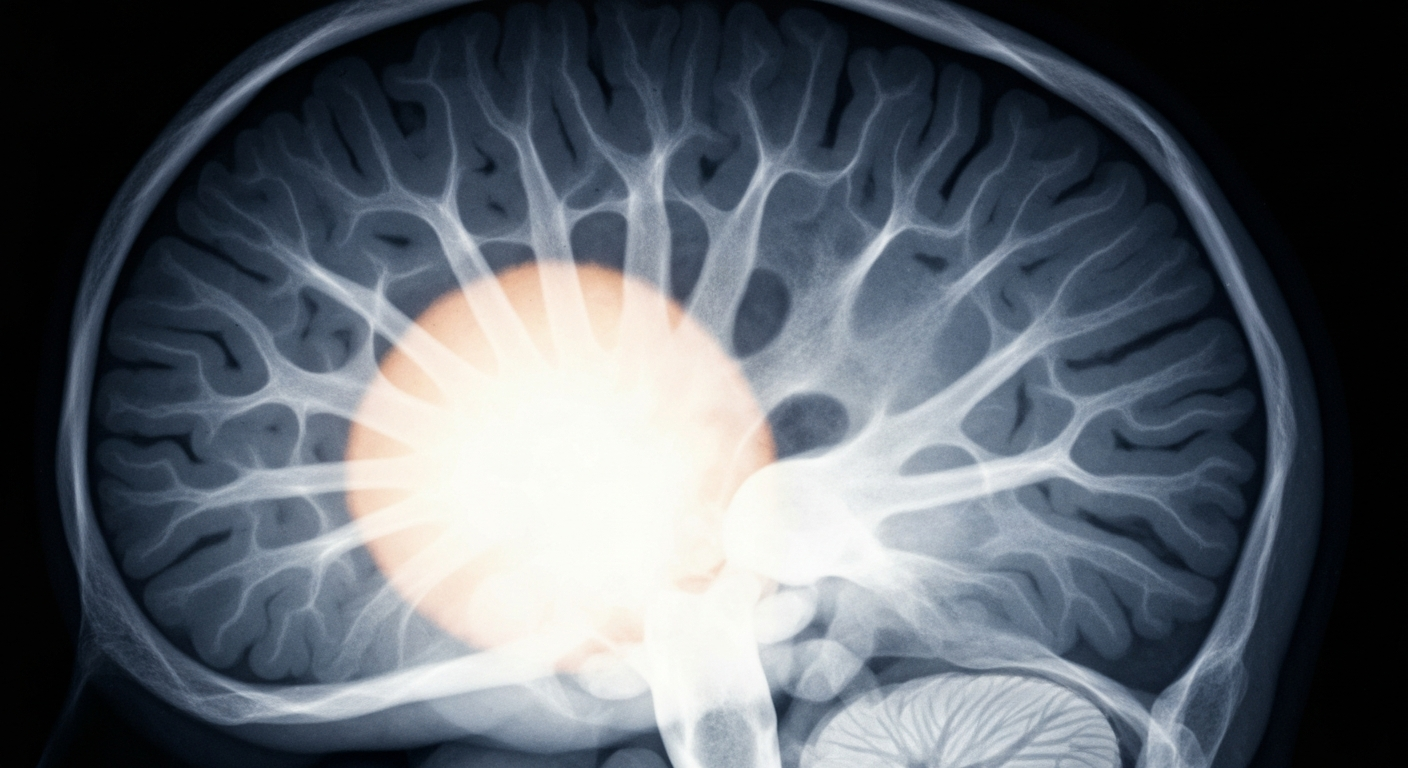

Bryan City Manager diagnosed with brain mass

Andrew Nelson, the former mayor, is undergoing medical evaluation after scans revealed a concerning growth.

A medical scan reveals a concerning mass within the brain of Bryan's city manager, raising questions about his health and ability to lead the community.Bryan TodayBryan City Manager Andrew Nelson, who previously served as the town's mayor, is currently undergoing medical evaluation after recent scans revealed the presence of a mass in his brain. The discovery has prompted concern and a need for further testing to determine the nature and severity of the condition.

Routine medical scans recently conducted on Andrew Nelson, the current City Manager of Bryan, Texas, uncovered the presence of a mass in his brain. Nelson, who previously served as the town's mayor, is now undergoing further evaluation by medical professionals to determine the nature and severity of the growth.